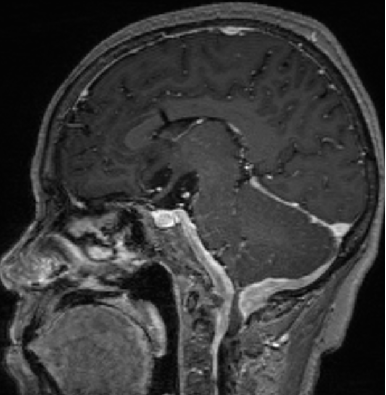

2013-8-2 CT

腰穿脑压240